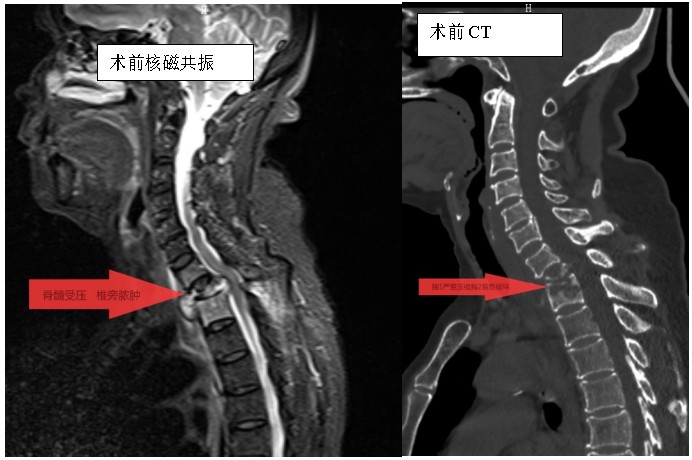

家住耒陽的70歲的李奶奶,因“頸胸背部疼痛不適伴雙上肢麻木6個月”,來到衡陽市中心醫(yī)院脊柱外科住院,住院當天,患者頸胸椎核磁共振顯示:胸1、2椎體骨質(zhì)破壞,伴胸1、2椎旁軟組織腫脹、同層面椎管變窄,因脊髓受壓而導致頸胸背部疼痛。在錢軍博士帶領(lǐng)下,醫(yī)療團隊詳細予以完善相關(guān)檢查后,研究患者的臨床資料,考慮脊柱結(jié)核并椎旁膿腫的可能性大,由于患者胸1椎體病理性骨折并椎管狹窄,遂囑患者嚴格臥床休息,術(shù)前給予標準四聯(lián)抗結(jié)核藥物治療2周,以控制活動性結(jié)核感染,降低術(shù)中播散風險,并嚴密監(jiān)測肝腎功能及血常規(guī)情況。

錢軍博士組織團隊進行了詳盡的術(shù)前討論,充分的術(shù)前準備后,于8月10日為患者實施了“前路病灶清除、人工椎體植入、植骨融合內(nèi)固定術(shù)”。順利完成了徹底清除病灶,椎管減壓解除脊髓壓迫,矯正后凸畸形,重建脊柱穩(wěn)定性的手術(shù)目標。